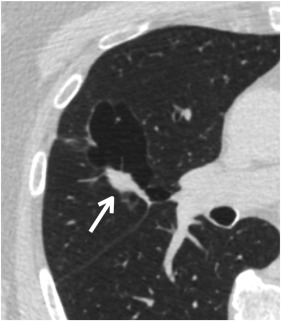

- Nang phổi không điển hình có nốt liên quan nằm trong lòng nang (u hướng vào bên trong) hoặc liền kề với thành (u hướng ra bên ngoài) được phân loại và quản lý theo phát hiện đáng ngờ nhất. Có thể khó phân biệt giữa nang có nốt thành (ví dụ: nang thành dày, Lung-RADS 4A) và nang thành mỏng có nốt sát bên (quản lý theo kích thước và thành phần nốt). Khi nghi ngờ, hãy chọn phân loại Lung-RADS cao hơn (Hình 4).

Hình 4. Nang có nốt liên quan. Một bệnh nhân 71 tuổi có nang phổi không điển hình dạng nhiều ngăn chứa thành phần đặc có đường kính trung bình 17 mm (mũi tên). Các nốt có thể phát sinh bên trong thành (thành dày), trong lòng (u hướng vào bên trong – endophytic) hoặc bên ngoài (u hướng ra bên ngoài – exophytic) của nang phổi. Phân loại và quản lý được xác định bởi đặc điểm đáng lo ngại nhất. Trong ví dụ này, nang nhiều ngăn được phân loại là Lung-RADS 4A; tuy nhiên, sự hiện diện của một nốt đặc có đường kính trung bình ≥ 15 mm cho phép phân loại 4B.